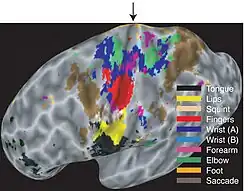

No córtex motor primário, a representação do motor é organizada ordenadamente (de forma invertida) do dedo do pé (na parte superior do hemisfério cerebral) até a boca (na parte inferior) ao longo de uma dobra no córtex chamado sulco central. No entanto, algumas partes do corpo podem ser controladas por regiões parcialmente sobrepostas de córtex. [3]Cada hemisfério cerebral do córtex motor primário contém apenas uma representação motora do lado oposto (contralateral) do corpo. A quantidade de córtex motor primário dedicado a uma parte do corpo não é proporcional ao tamanho absoluto da superfície do corpo, mas, em vez disso, à densidade relativa dos receptores motores cutâneos na referida parte do corpo. A densidade dos receptores motores cutâneos na parte do corpo é geralmente indicativa do grau necessário de precisão de movimento requerido na parte do corpo. Por esta razão, as mãos e o rosto humanos têm uma representação muito maior do que as pernas.

Homúnculo

Existe uma representação amplamente somatotópica das diferentes partes do corpo no córtex motor primário em um arranjo chamado homúnculo motor (latim: pessoa pequena).[5] A área da perna está localizada perto da linha média, nas seções interiores da área do motor dobrando a fissura longitudinal medial. O lado lateral e convexo do córtex do motor primário é organizado de cima para baixo em áreas que correspondem às nádegas, torso, ombro, cotovelo, pulso, dedos, polegar, pálpebras, lábios e mandíbula. A área do braço e do motor de mão é a maior, e ocupa a parte do giro pré-central entre a área da perna e do rosto.

Essas áreas não são proporcionais ao seu tamanho no corpo com os lábios, as partes do rosto e as mãos representadas por áreas particularmente grandes. Após amputação ou paralisia, as áreas motoras podem mudar para adotar novas partes do corpo.

Pelo menos duas modificações à ordem somatotópica clássica das partes do corpo foram relatadas no córtex motor primário de primatas.

Primeiro, a representação do braço pode ser organizada de forma central. No córtex dos macacos, os dígitos da mão estão representados em uma área central na borda posterior do córtex motor primário. Esta área central é cercada em três lados (nos lados dorsal, anterior e ventral) por uma representação das partes mais proximais do braço, incluindo o cotovelo e o ombro.[6][7] Nos seres humanos, a representação do dígito é cercada dorsalmente, anterior e ventralmente, por uma representação do pulso.[8]

Uma segunda modificação da ordem somatotópica clássica das partes do corpo é uma dupla representação dos dígitos e pulso estudados principalmente no córtex motor humano. Uma representação encontra-se numa região posterior chamada área 4p, e a outra encontra-se numa região anterior chamada área 4a. A área posterior pode ser ativada por atenção sem qualquer feedback sensorial e tem sido sugerida como importante para o início dos movimentos, enquanto a área anterior depende do feedback sensorial.[9] Também pode ser ativado por movimentos imaginários[10] dos dedos e ouvir a fala sem fazer movimentos reais. Esta área de representação anterior foi sugerida para ser importante na execução de movimentos envolvendo interações sensoriomotoras complexas.[11] É possível que a área 4a em seres humanos corresponda a algumas partes do córtex pré-motor caudal como descrito no córtex de macaco.

Mapa segregado do corpo

Um dos equívocos mais comuns sobre o córtex motor primário é que o mapa do corpo é perfeitamente segregado. No entanto, não é um mapa de músculos individualizados ou mesmo partes do corpo individualizadas. O mapa contém uma sobreposição considerável. Essa sobreposição aumenta em regiões mais anteriores do córtex motor primário. Um dos principais objetivos da história do trabalho no córtex motor foi determinar o quanto as diferentes partes do corpo estão sobrepostas ou segregadas no córtex motor. Os pesquisadores que abordaram esta questão descobriram que o mapa da mão, braço e ombro continha ampla sobreposição.[5][7][8][14][15][16][17][18] Estudos que mapeiam a conectividade funcional precisa dos neurônios corticais aos músculos mostram que mesmo um único neurônio no córtex motor primário pode influenciar a atividade de muitos músculos relacionados a muitas articulações.[14] Em experimentos com gatos e macacos, à medida que os animais aprendem movimentos complexos e coordenados, o mapa no córtex motor primário se torna mais sobreposto, evidentemente aprendendo a integrar o controle de muitos músculos.[19][20] Em macacos, quando a estimulação elétrica é aplicada ao córtex motor em uma escala de tempo de comportamento, ele evoca movimentos complexos, altamente integrados, como alcançar a mão em forma de agarrar ou levar a mão à boca e abrir a boca.[21][22] Este tipo de evidência sugere que o córtex motor primário, ao mesmo tempo que contém um mapa áspero do corpo, pode participar na integração de músculos de maneiras significativas ao invés de segregar o controle de grupos musculares individuais. Sugeriu-se que um princípio mais profundo de organização pode ser um mapa das correlações estatísticas no repertório comportamental, em vez de um mapa das partes do corpo.[22][23] Na medida em que o repertório do movimento quebra em parte nas ações de partes do corpo separadas, o mapa contém um arranjo de corpo áspero e sobreposto.